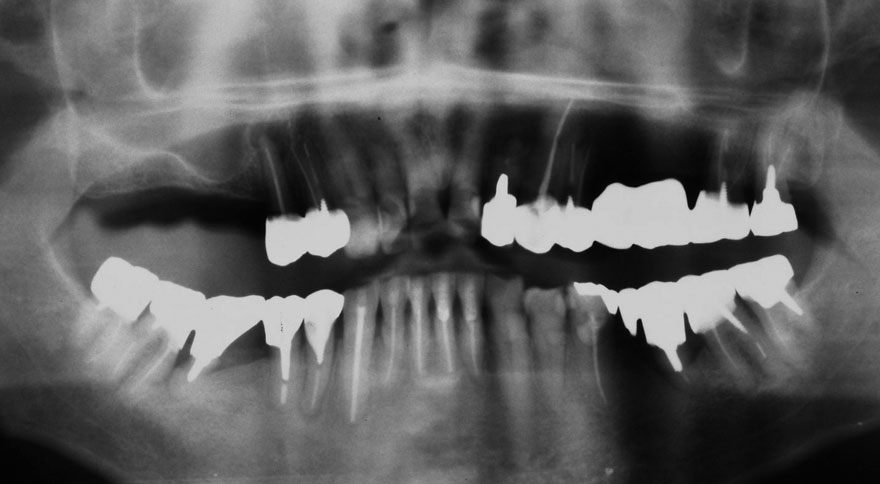

初診時 50歳 女性

30年後 80歳